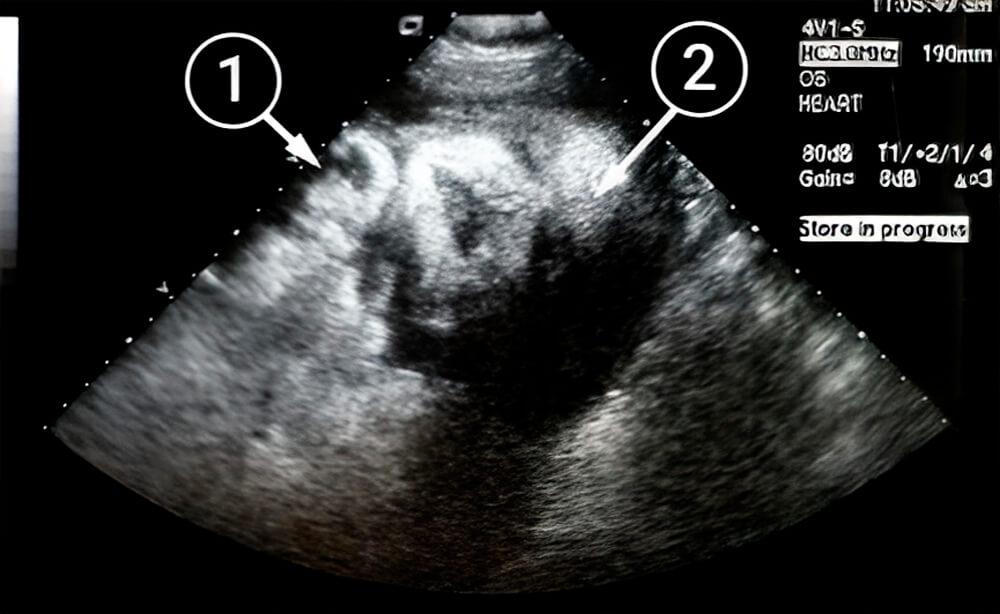

Lo que podemos ver en un ultrasonido

Esta imagen muestra un primer plano de la cabeza del bebé. Sus rasgos faciales están completamente formados: los ojos, la nariz y la frente son visibles. El bebé tiene apoyada la barbilla sobre la mano.